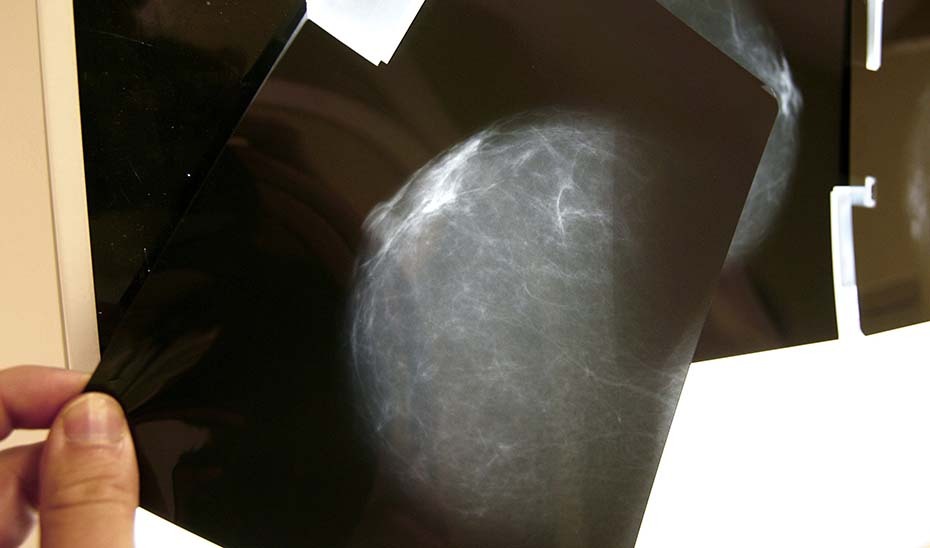

Actualmente, cuando se realiza una mamografía a una mujer dentro del programa de cribado del cáncer de mama existen tres posibles diagnósticos: negativo, positivo y lesión posiblemente benigna.

En el caso de diagnósticos negativos, las pacientes son informadas del resultado; en el caso de diagnósticos positivos, las mujeres son igualmente informadas y derivadas para nuevos procedimientos pero, en los casos en los que se detectan lesiones posiblemente benignas las mujeres pueden no haber sido informadas de que su caso sigue un procedimiento clínico con supervisión médica.

La consejera ha explicado que, en estos casos, hasta tres radiólogos analizan las imágenes y, en función de los factores de riesgo de cada paciente, deciden el tiempo que ha de transcurrir para la segunda prueba. Las pacientes, que viven ajenas a estas circunstancias, reciben al cabo de meses o de un año una llamada que no esperan para esa segunda cita -fijada por el radiólogo- y sienten alarma, intranquilidad y angustia.

"Es algo normal y creemos que hay que corregirlo, porque se puede corregir", ha señalado la consejera, que ha anunciado que "desde hoy se ha empezado a llamar a todas estas mujeres", unas 2.000 en toda Andalucía, para informales de que en su día se les detectó una lesión probablemente benigna, que sus casos están siendo atendidos por un equipo médico y que, en el tiempo que han marcado los facultativos, volverán a ser llamadas para una nueva prueba. El 98% de estos casos terminan siendo diagnosticados como benignos.